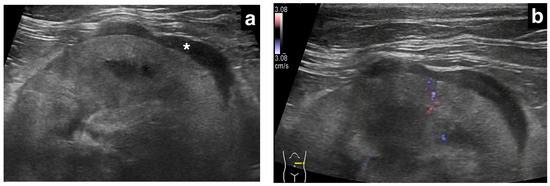

肾转移性肺癌的超声图像

超声检查共评估9个肾脏(双侧3例,左侧2例,右侧1例)。被膜下增厚最大厚度1.0-13.2 mm(中位数3.0 mm),其中原发性肾细胞癌病例增厚最显著(13.2 mm),转移性癌均小于5 mm。分布特征上,8个转移性癌肾脏表现为局灶性、均匀低回声增厚,1个原发性肾癌肾脏呈环周性、不均匀混合回声增厚。肾皮质边缘和包膜边缘各见5例光滑、4例不规则。5个肾脏行彩色多普勒检查,2例增厚病灶内可见血流信号,仅1例双侧出现肾周积液。

本研究报道了猫原发性或转移性癌可导致肾脏低回声被膜下增厚。研究发现,转移性癌(主要来源于肺腺癌)多表现为局灶性、均匀低回声增厚(厚度<5 mm),而原发性肾癌可表现为环周性、不均匀混合回声增厚。组织病理学证实,增厚层内可见肿瘤细胞浸润或坏死组织,提示该征象可能源于肿瘤细胞沿肾被膜下淋巴系统播散。